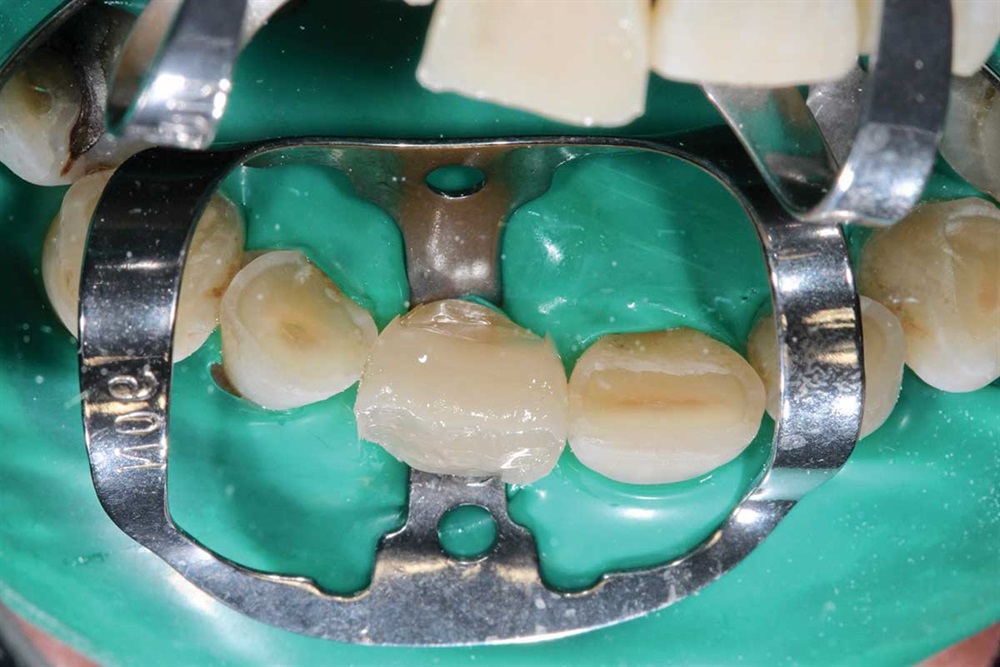

Fig. 27: Starting the maxillary teeth with 90N, rubber dam and Premier Cure-Thru contoured matrix band. Incisal view.

Fig. 28: My first increment is Z250 to provide palatal support, and then I cover that with Renamel A1.5.